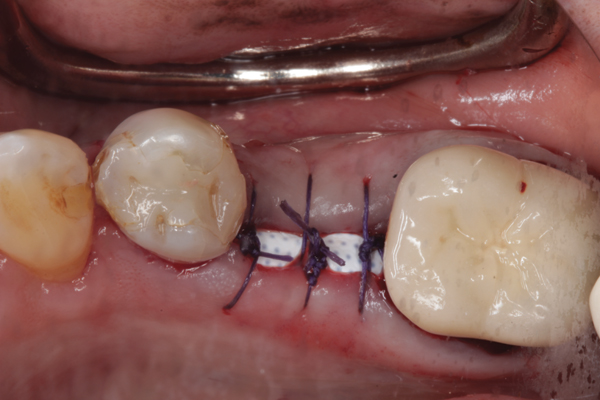

Fig 1. (Case 1) Tooth No. 19 manifested a buccal fistulous tract. Probing depth on the buccal was 8 mm.

Figure 1

Fig 6. d-PTFE barrier in position, and the flap sutured.

Figure 6

The four presented cases shown in Figure 1 through Figure 25 were all treated in a similar manner as outlined in detail in the captions for the first case (Figure 1 through Figure 11). In all four cases, teeth with pathosis were removed, buccal and lingual flaps were elevated, and sites were surgically debrided. A Cytoplast d-PTFE barrier was sized and inserted usually under the buccal flap, the bone graft was added, the barrier was then tucked under the lingual flap, and the flaps were sutured. Bone grafts were used in all of the cases, because buccal bony plates were resorbed and the bone graft helped support the barrier.